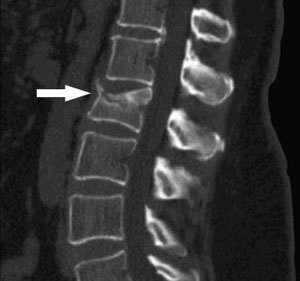

compresssion fracture

chance francture

from seatbelt